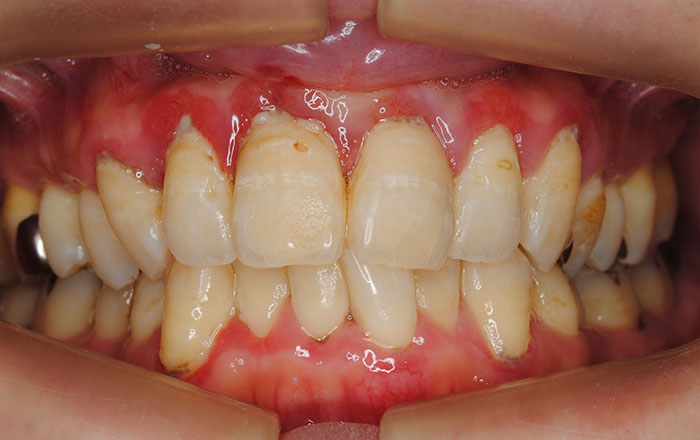

妊娠性歯肉炎

妊娠性歯肉炎は、一般的に妊娠2ヶ月目から顕著になり、8ヶ月で最大になるといわれています。

◇症状としては…

①歯肉が赤黒く腫れ、出血しやすい(部分的に症状が出ることもあります)

③痛みはみられないことが多い